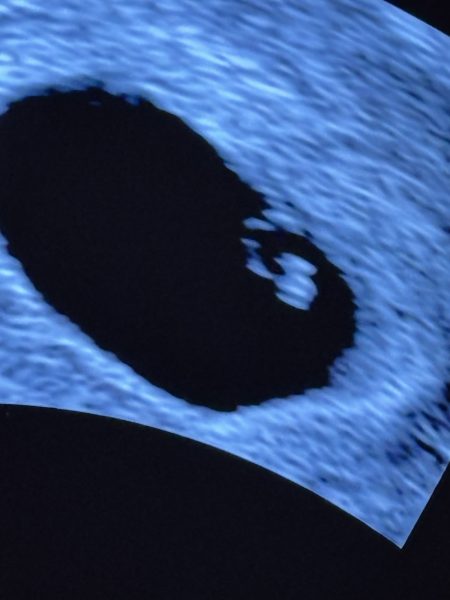

Idag följde jag Ida på ett första tidigt ultraljud som visar att hon precis gått in i vecka 7 av hennes graviditet. Ett litet hjärtslag syntes också ❤️